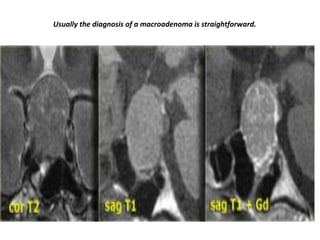

Usually the diagnosis of a macroadenoma is straightforward.

Usually the diagnosisof a macroadenoma is straightforward.